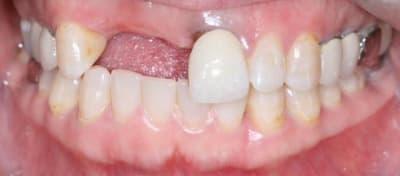

On avance dans le cas, j'ai revu la patiente hier.

Elle est satisfaite et moi pas vraiment, comme quoi...

Elle ne veut pas faire de chir mucco gingivale et accepte éventuellement que je fasse une petite chir d'élongation coronaire sur 21 car elle trouve cela surperflux.

Tristesse et difficulté des sourires gingivaux !

J'avais bien raison de me méfier au départ...

Dommage pour la teinte...

Une greffe osseuse aurait bcp aider, les implants sont trop enfouis par rapport à la 21.

Si la patiente est contente, alors...